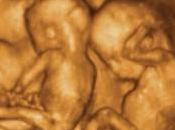

Gli abortisti in affanno osteggiano l’uso dell’ecografia 4D

L’avanguardia scientifica mette anno dopo anno sempre più in crisi il movimento abortista, come dimostrato in Ultimissima 11/03/12 accennando alla recente... Leggere il seguito

Il 14 marzo 2012 da Uccronline